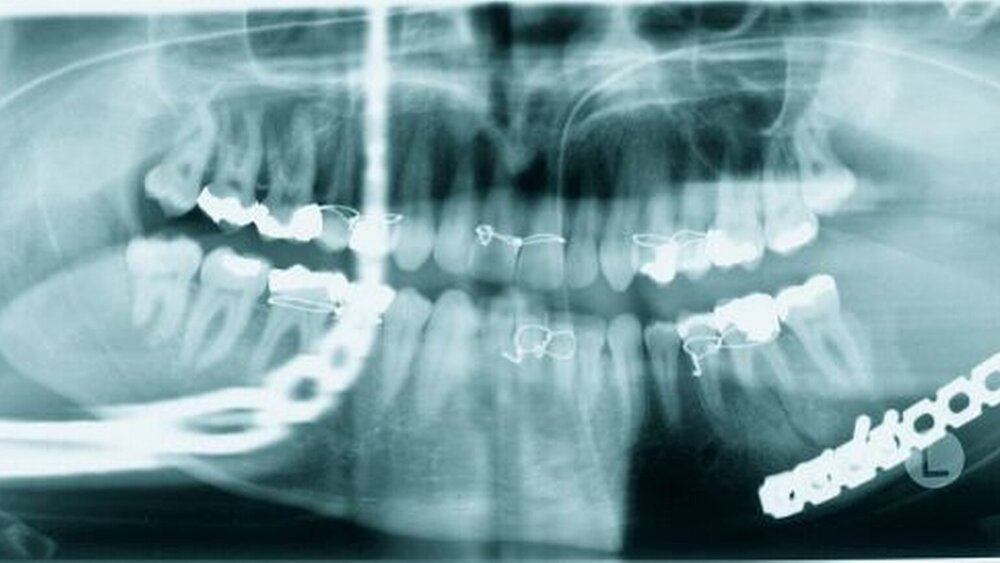

Das durchgeführte Orthopantomogramm (Abbildung 2) identifizierte eine nahezu komplette Osteolyse des expandierten linken aufsteigenden Unterkieferastes mit ausgedünnter Kortikalis und teilweiser Perforation derselben. Die sich anschließende Computertomographie des Kopf-Hals-Bereiches (Abbildung 3) beschrieb eine vom linken Kieferwinkel ausgehende, relativ scharf begrenzte und überwiegend verdrängend wachsende Raumforderung von etwa 5,5 x 4,5 x 6,0 cm³ Größe mit Durchbruch der dorsalen Kieferhöhlenwand und Erstreckung bis in die Fossa infratemporalis. Es folgte eine Inzisionsbiopsie über einen intraoralen Zugang. Die histopathologische Begutachtung der Biopsie ergab ein desmoplastisches Fibrom ausgehend vom linken Unterkieferwinkel (Abbildung 4).

Daraufhin wurde eine Unterkieferteilresektion einschließlich des aufsteigenden Astes und des Kondylus (Abbildung 5) sowie eine temporäre Rekonstruktion mittels Kondylenplatte durchgeführt (Abbildung 6).